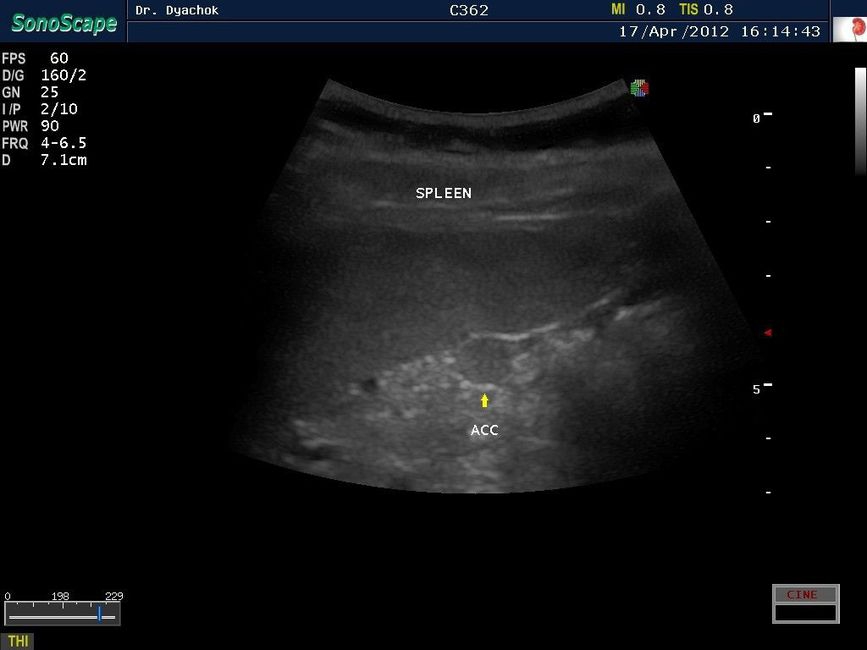

Sonoscape S9 представляет собой топовую переносную ультразвуковую систему, сочетающую инновационный дизайн, современные технологии визуализации и широкие диагностические возможности. Компактный аппарат экспертного класса подтверждает лидирующие позиции компании на рынке портативных ультразвуковых систем.

• Исследования поверхностных и абдоминальных органов